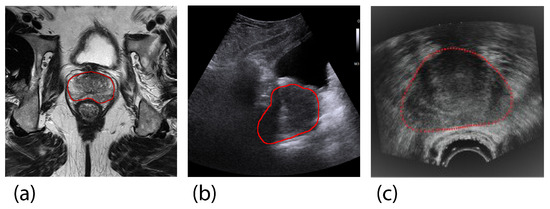

- Liu, D.; Wang, L.; Du, Y.; Cong, M.; Li, Y. 3-D Prostate MR and TRUS Images Detection and Segmentation for Puncture Biopsy. IEEE Trans. Instrum. Meas. 2022, 71, 5016613. [Google Scholar] [CrossRef]